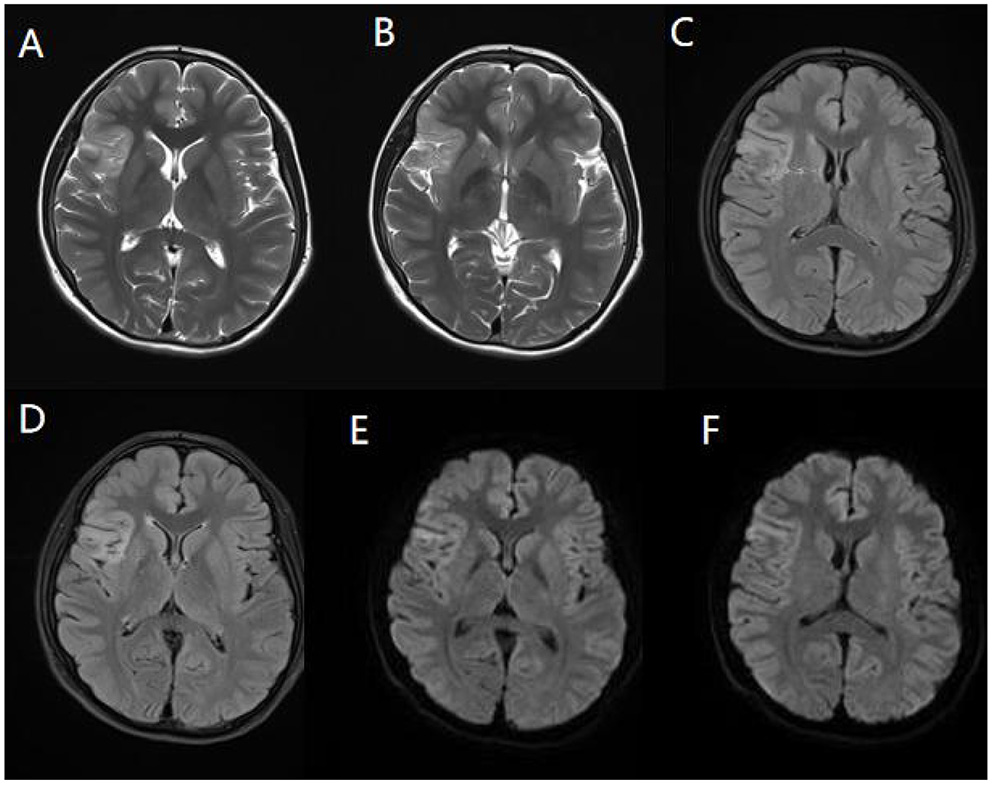

Cerebrospinal fluid (CSF) examination was performed in 102 of our 103 AE patients (prior to IVIG application). CSF pleocytosis (white blood cell count >5/mm3) was observed in 74 patients, and the maximum white blood cell count observed was 137/mm3. Elevated CSF protein levels (>500 mg/L) were observed in 9 patients, with the highest protein level being 820 mg/L. Brain MRI and EEG were performed and evaluated in all 103 patients. Brain MRI abnormalities were observed in 45 patients. Typical imaging findings of patients included in the study are shown in Figure 3. In the anti-NMDAR encephalitis group, abnormal brain MRI findings were observed in 43.3% of patients: abnormal fluid-attenuated inversion recovery (FLAIR) sequence signals associated with anti-NMDAR encephalitis were mainly found in the parietal, frontal, or temporal lobes. In the anti-CASPR2 encephalitis group, brain MRI abnormalities were observed in 2 patients (40%). All patients in the anti-GABABR and anti-LGI1 encephalitis groups had abnormal MRI findings in our study. EEG abnormalities were observed in 96 patients (93.2%). The most common abnormal EEG findings were focal or generalized non-specific slow waves (91.3%) and epileptiform discharges (such as sharp waves, spike waves, sharp slow wave complexes, or spike slow wave complexes) (41.7%).Twelve patients had seizures during video-EEG monitoring. A typical abnormal EEG showed diffusely slow waves and diffuse spike waves in Figure 4.

Figure 3

Magnetic resonance imaging (MRI) of a representative pediatric patient admitted for convulsions for 2 weeks and diagnosed with anti-NMDA receptor encephalitis (NMDA receptor antibody in CSF was 1:100). Right temporal and insula lobes and frontal cingulate gyrus showed lamellar abnormal signasl. T2WI showed a high signal (A,B). FLAIR sequence was dominated by a high signal (C,D), and DWI showed a high signal (E,F).